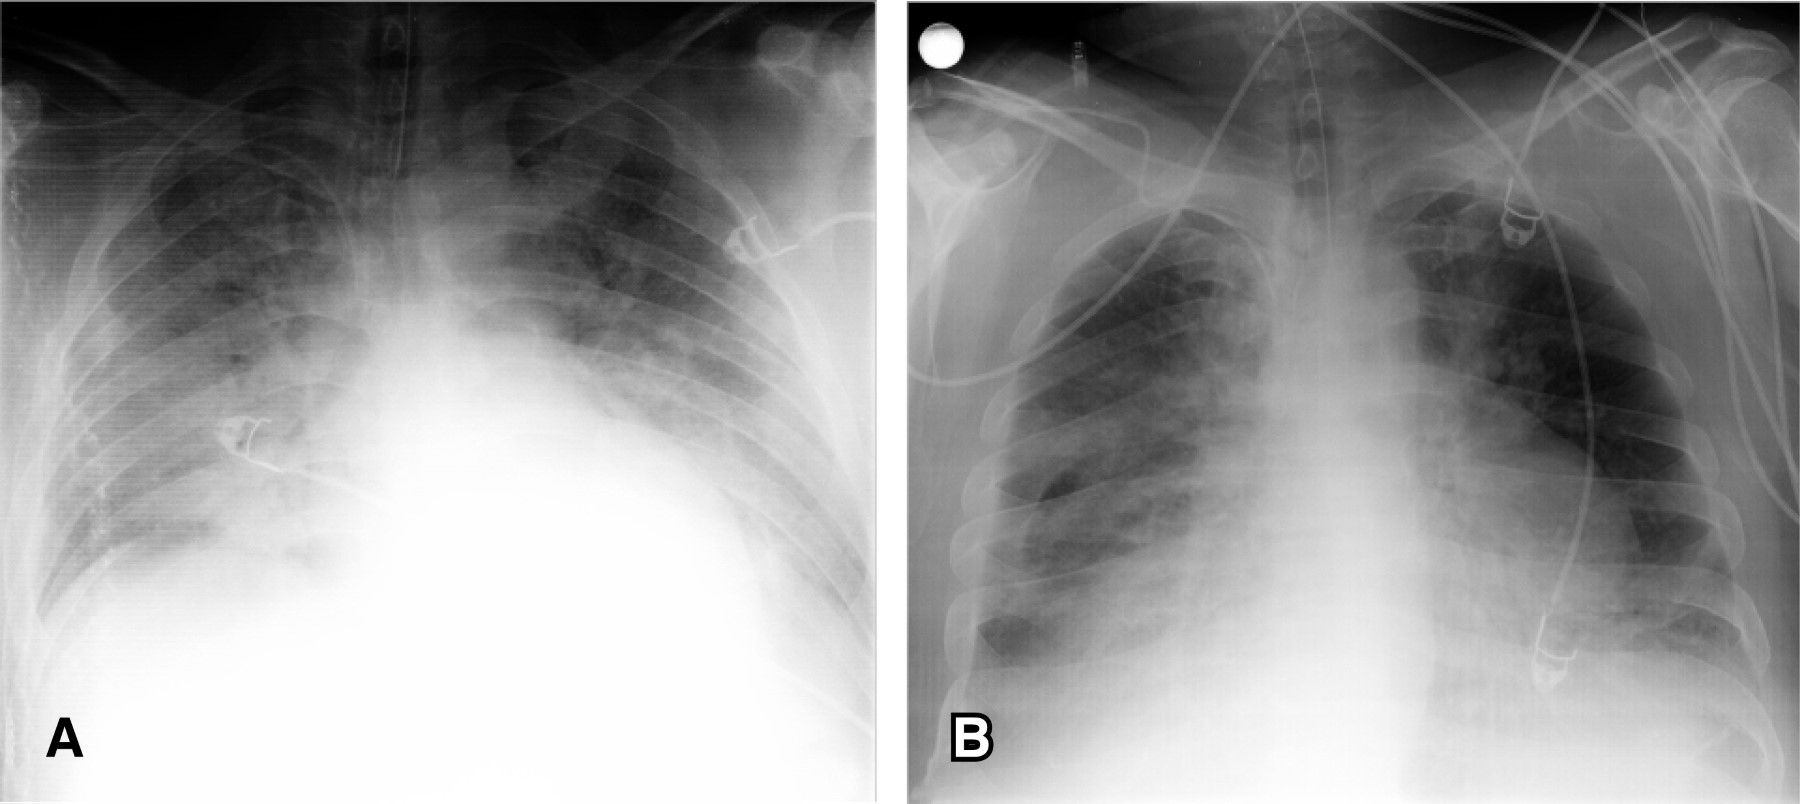

En el acmé de la segunda ola de la COVID-19, un paciente masculino de 42 años previamente saludable y con índice de masa corporal de 23 kg/m2 fue admitido en la sala de emergencias con un cuadro de HSA. Hunt-Hess III, Fisher IV, y World Federation of Neurosurgeons 2; ingresó con una escala de coma de Glasgow (ECG) de ocho puntos y síntomas respiratorios altos leves, con prueba antigénica positiva para la COVID-19 y tomografía pulmonar con signos típicos de COVID-19 en poco volumen (Figura 1), la ECG mejoró hasta los 14 puntos, aunque estuvo somnoliento y confuso. Inició tratamiento con analgesia parenteral y nimodipino.

Figura 1